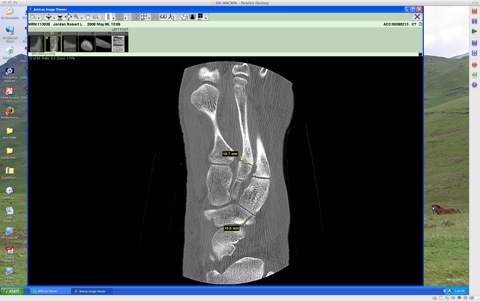

The above are frames from my CT scan (Think of them as Oscar Meyer balogna-like slices through my foot) showing a few of the nastier tid-bits. The medical jargon from the CT analysis follows:

FINDINGS: There is a sagittal hairline fracture through the lateral navicular with comminution at its dorsal and plantar margins with multiple tiny comminuted fracture fragments off its dorsal aspect and widening of the fracture line to 1 mm at its plantar lateral aspect. This fracture line reaches both the articular surface of the talonavicular joint and tarsonavicular joint. The plantar margin of this navicular fracture adjoins a small area of comminuted fracture of the dorsal lateral distal calcaneal margin, seen on axial images 35 to 44. There is a small adjoining area of comminution of the proximal dorsal lateral margin of the cuboid.

There is a small hairline oblique fracture through the plantar margin of the base of the first metatarsal, best seen on sagittal images 13 through 15. There is a hairline intra-articular oblique fracture through the base of the second metatarsal, best seen on sagittal images 22-25. There is a comminuted fracture through the medial plantar margin of the base of the third metatarsal with an 11 mm x 7 mm x 4 mm and smaller fragments slightly medially displaced, best seen on axial images 38-45 and coronal images 31-37.